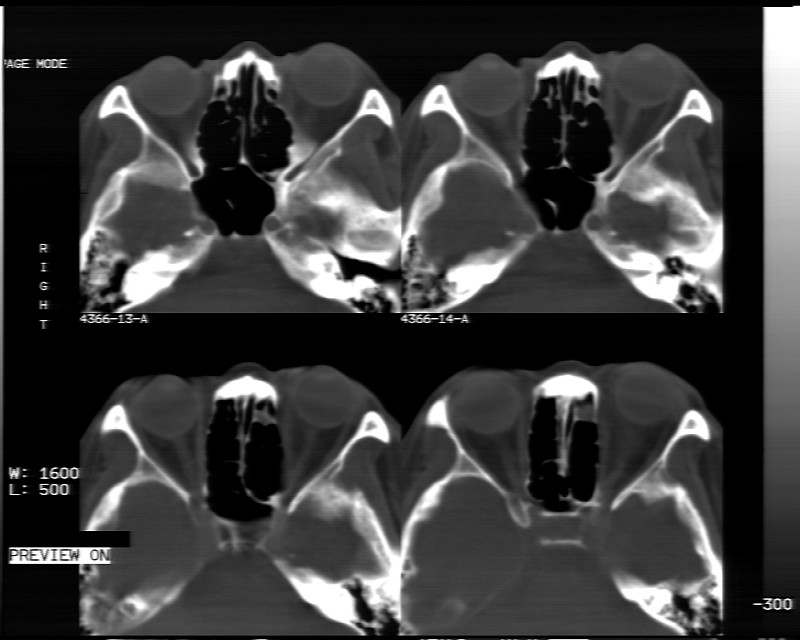

女性,40岁,左眼疼痛,视力模糊,五年曾行左眼脂肪瘤手术。

患者现病史不知持续有多久了,现片示眶内病灶边缘较模糊,眶脂混浊,多考虑炎性假瘤,不除外肿瘤

1)左眼眶内占位性病变,性质待定(不排除炎性假瘤);建议行进一步检查。2)左侧额窦炎。